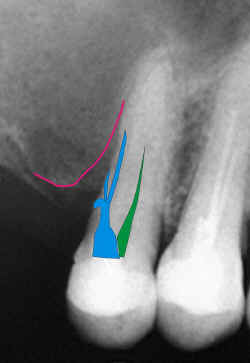

Fratura de instrumento endodôntico metálico com

trepanaçăo apical e conseqüente reaçăo tissular. Fratura de instrumento endodôntico metálico com

trepanaçăo apical e conseqüente reaçăo tissular.

Observe

a angulaçăo do instrumento fraturado. Observe

a angulaçăo do instrumento fraturado.

A

certeza de que a imagem corresponde a um instrumento metálico reside na relaçăo entre

suas dimensőes e radiopacidade. A

certeza de que a imagem corresponde a um instrumento metálico reside na relaçăo entre

suas dimensőes e radiopacidade. |

Esquema gráfico evidenciando ao leigo as alteraçőes

visualizáveis na radiografia. Esquema gráfico evidenciando ao leigo as alteraçőes

visualizáveis na radiografia.

A

imagem é clara e o fato constitui erro odontológico, passível de responsabilizaçăo do

profissional. A

imagem é clara e o fato constitui erro odontológico, passível de responsabilizaçăo do

profissional.